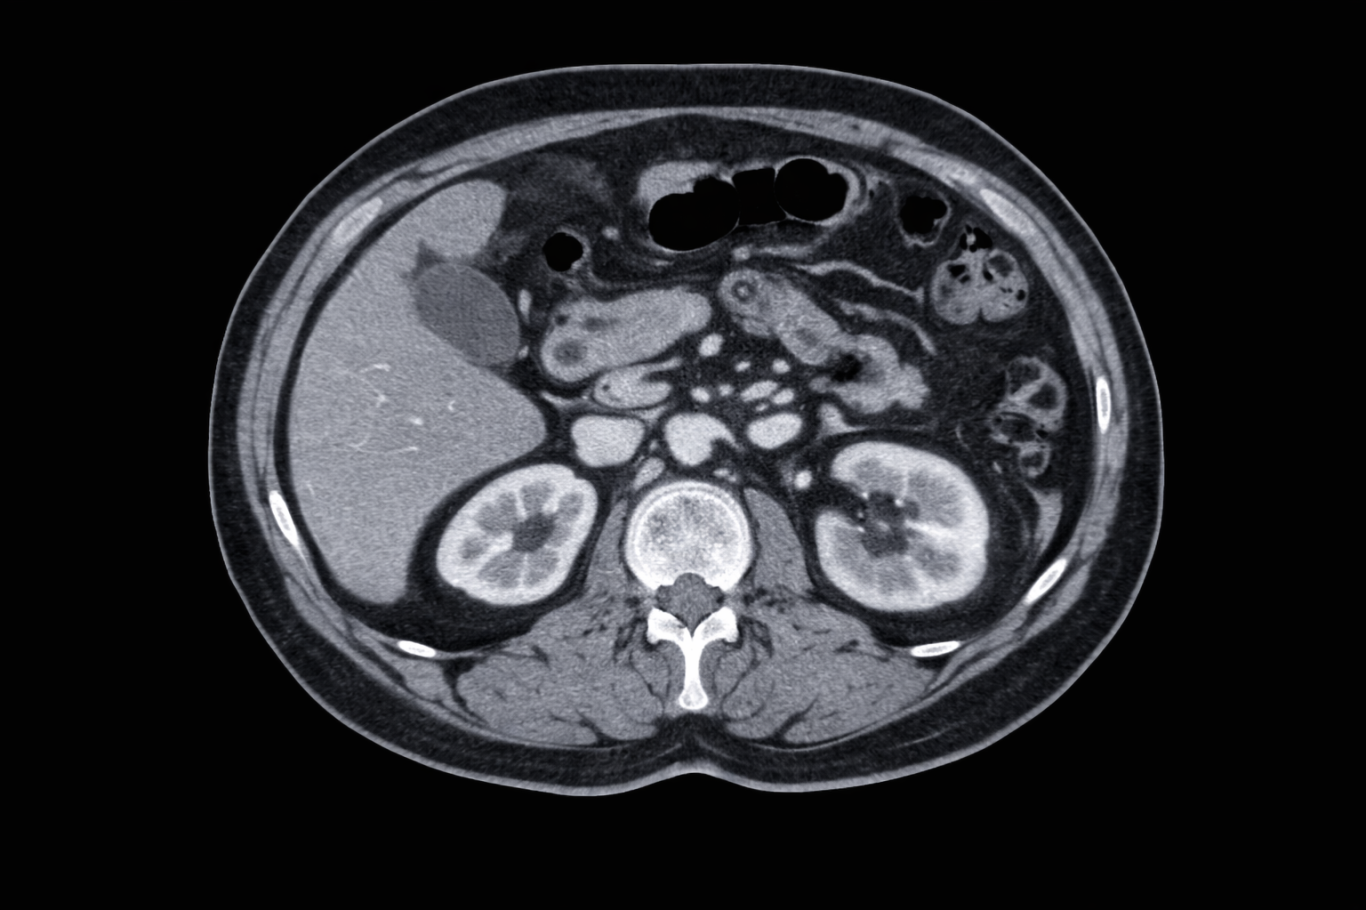

Scanner

Le scanner (tomodensitométrie) est un examen d’imagerie qui utilise des rayons X et un traitement informatique pour obtenir des images très précises en coupe du corps. Il permet d’explorer rapidement de nombreux organes, notamment le cerveau, les poumons, l’abdomen ou les os. Dans certains cas, une injection de produit de contraste peut être réalisée pour améliorer la visualisation des structures.